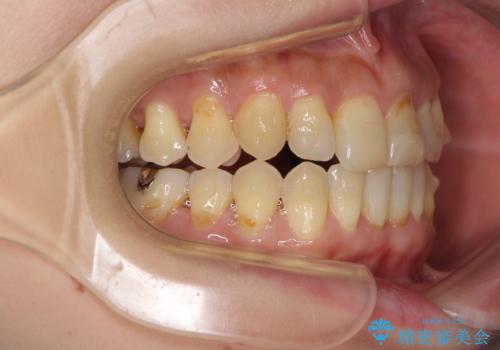

- 歯列不正と、どこで咬んで良いのか分からない咬み合わせを気にして来院された患者様です。

下顎骨は左側にシフトしており、咬み合ったときには奥歯と前歯の一部しか接触していない状態でした。

骨格的な左右差は歯列矯正は改善できないため、上下歯列が全体的に接触することをゴールとしてインビザラインにて矯正治療を行うこととしました。